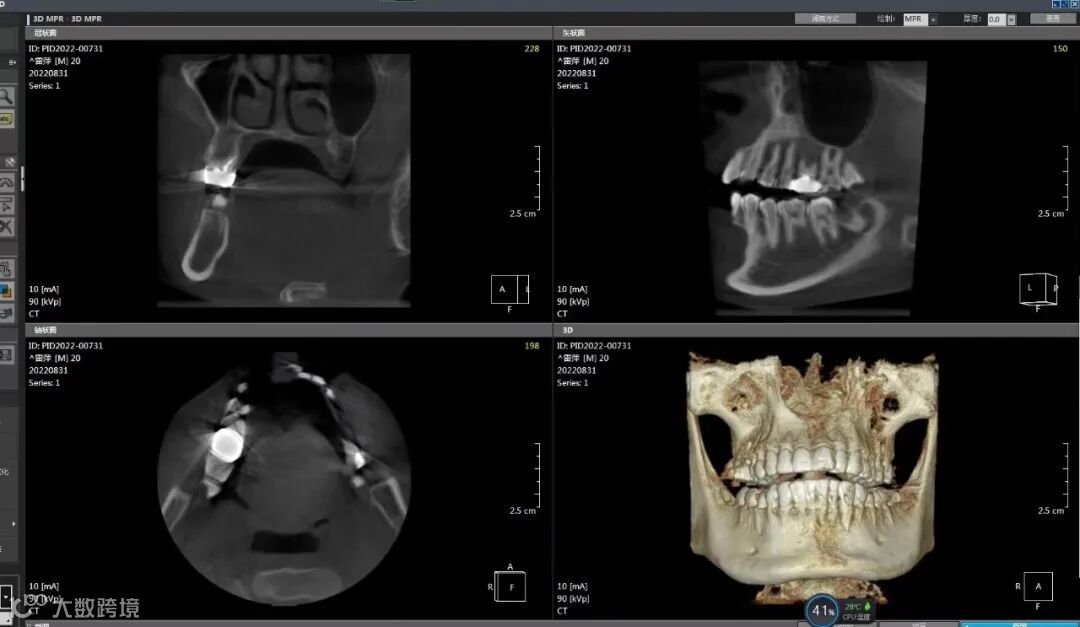

钡尔口腔斥巨资引进先进口腔检查治疗设备:韩国三星数字化口腔CBCT、数字化全景机、数字化X光检查系统、口腔3D扫描仪、国际标准的消毒设备、先进的根管治疗系统、瑞士EMS超声波洁牙机、舒适牙周治疗仪、进口微创种植系统、以及能完全达到无菌操作的口腔数字化综合治疗机,保证口腔治疗护理的安全可靠。